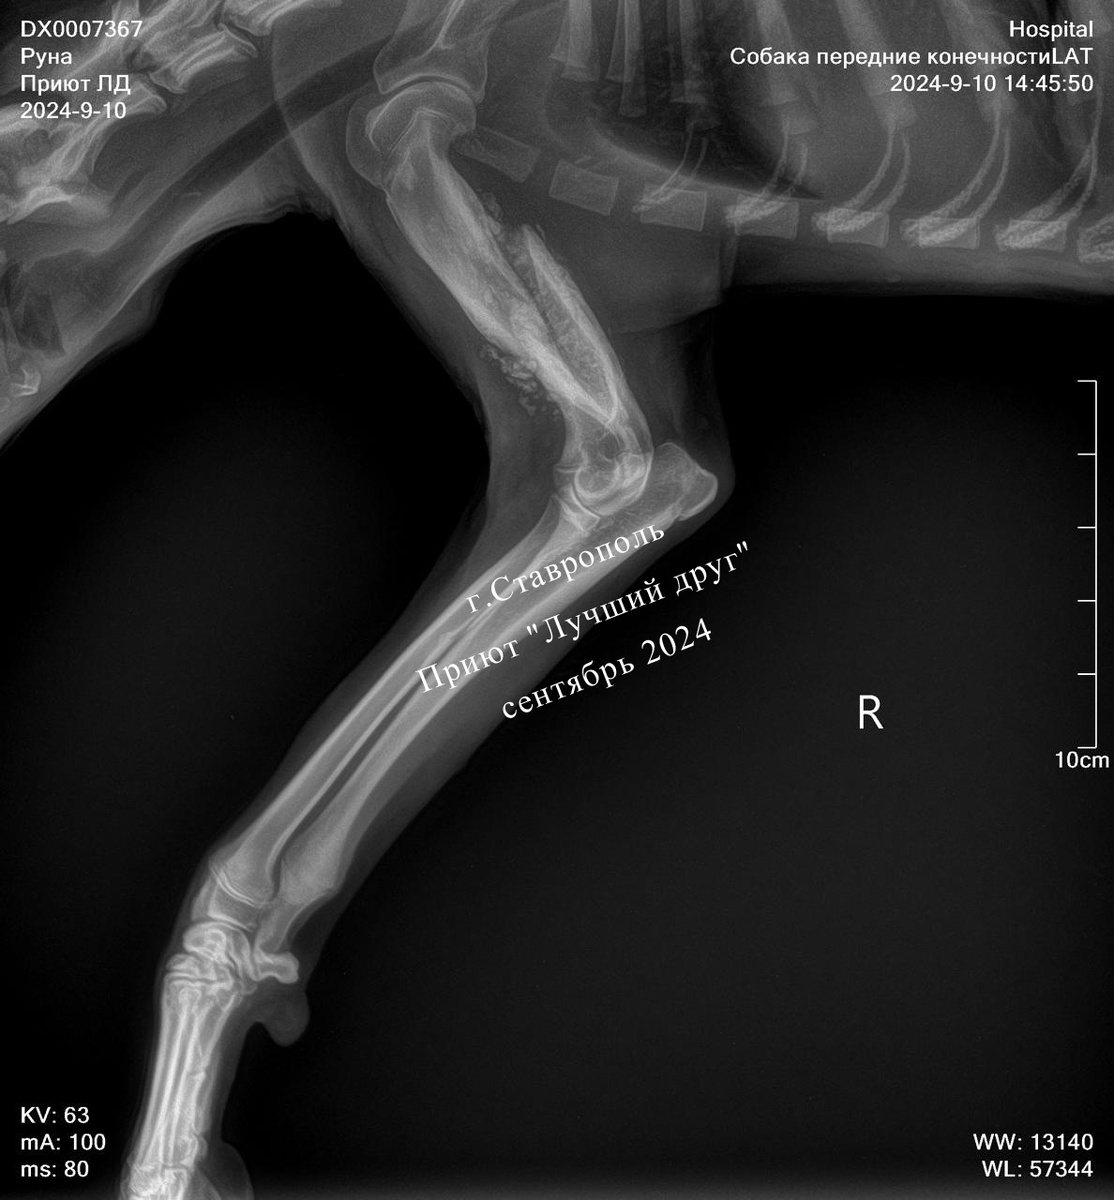

Это оказалась молодая собака, подросток, у нее застарелый перелом передней лапы, с которым, вероятнее всего, уже ничего сделать нельзя. Но основная проблема не в хромоте, а в запущенном пироплазмозе и анемии, у собаки очень плохие анализы, слизистые совершенно белые, как будто крови в собаке уже не осталось...